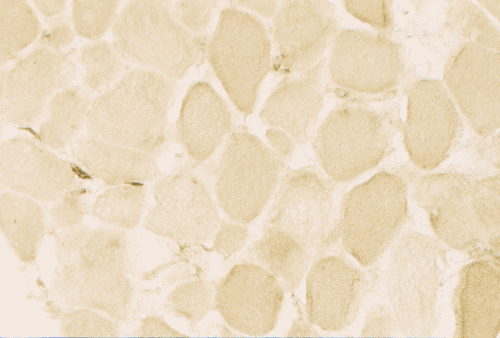

On ATPase reaction at pH 9.4, there is type I fiber predominance. This result is verified by ATPase reaction performed at pH 4.3 and 4.6.